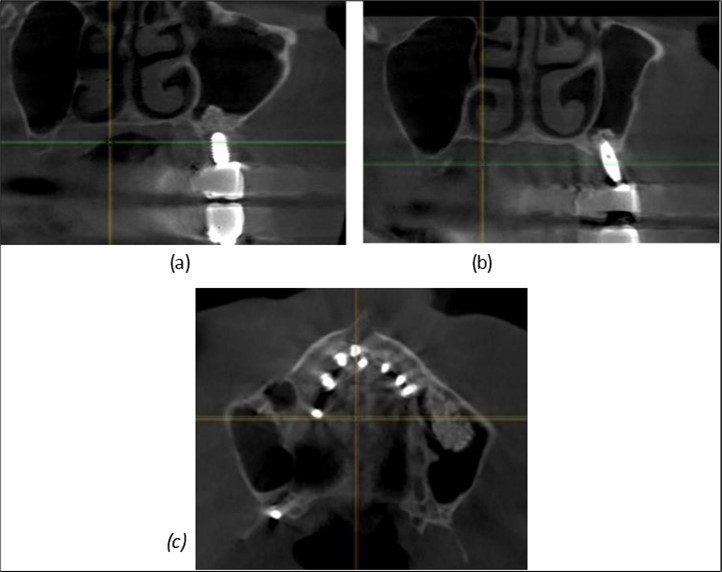

Figure 8.(a), (b) Sinus lift and grafting area with two stage implants before their removal. (c) area of fixation of BCS and TPG implants, avoiding the sinus lift and grafting area

Figure 9.Implants in the pterygoid plateau area: (a) TPG implant fixed in the maxillary-sphenoid junction area, quadrant 1; (b) TPG implant fixed in the maxillary-sphenoid junction area, quadrant 2.

Figure 10.Implants in the palatal sinus cortical area to avoid bone grafting: (a) BCS implant partially fixed in the graft material mass, partially in the palatal cortex; (b) Implant fixed in the palatal cortex at the junction with the nasal cortex, behind the graft material mass.

Figure 11.Implants in the anterior area anchored in the nasal cortex (BCS and TPG): (a), (c) – BCS implants fixed in the nasal cortex; (b), (d) – TPG implants fixed in the second nasal cortex with compression in the trabecular area.